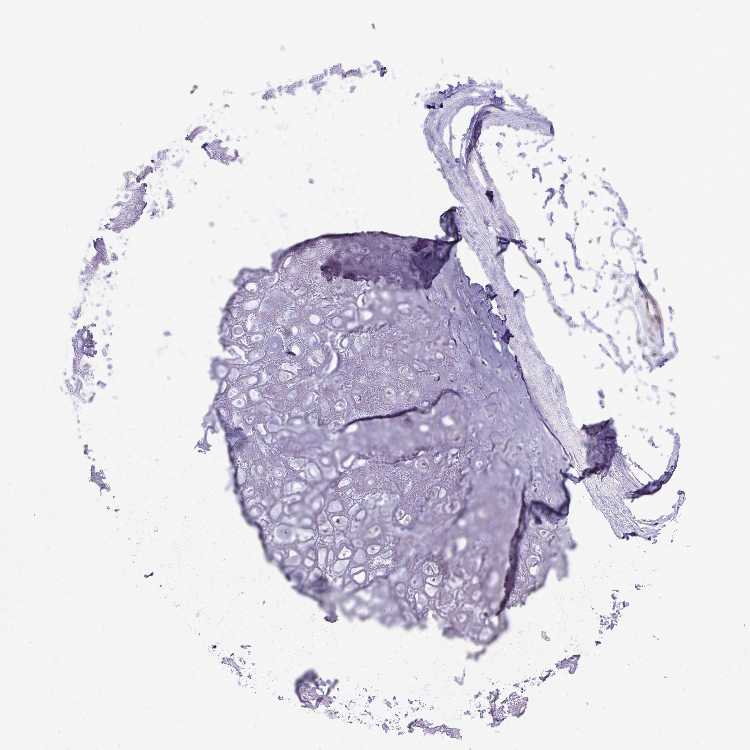

SOFT TISSUE 1 - Antibody stainingi

Antibody staining in the annotated cell types in the current human tissue is reported as not detected, low, medium, or high, based on conventional immunohistochemistry profiling in selected tissues. This score is based on the combination of the staining intensity and fraction of stained cells.

Each image is clickable and will lead to virtual microscopy that enables deeper exploration of all samples and also displays staining intensity scores, fraction scores and subcellular localization as well as patient and tissue information for each sample.

Antibody HPA030761Antibody HPA056168

Chondrocytes Not detectedLow

SOFT TISSUE 2 - Antibody stainingi

Fibroblasts Not detectedMedium

Peripheral nerve Not detectedNot detected